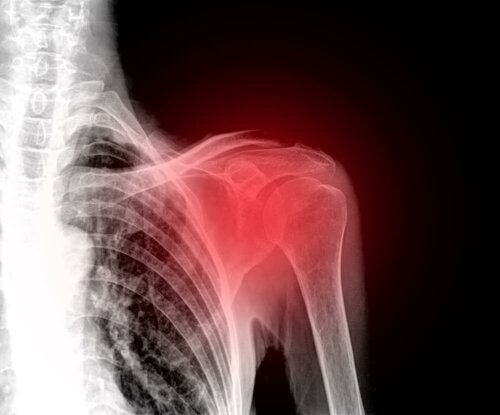

Donuk omuz, omuz ekleminin patolojik ve travmatik bir olay yaşamasının sonucudur. Ayrıca “adeziv kapsülit” adıyla da bilinir, çünkü semptomların nihai üretim mekanizması omuz kapsülünün iltihaplanmasıdır.

Bunu anlamak için omuzun yapısal formunu incelemeliyiz. Humerus, klavikula ve kürek kemiğinin kemikler ile temas ettiği, kapsülü oluşturan ve onları çevreleyen yumuşak doku ile çevrili olduğu bir eklemdir. Bu kapsül donuk omuzda kalınlaşan kapsüldür.